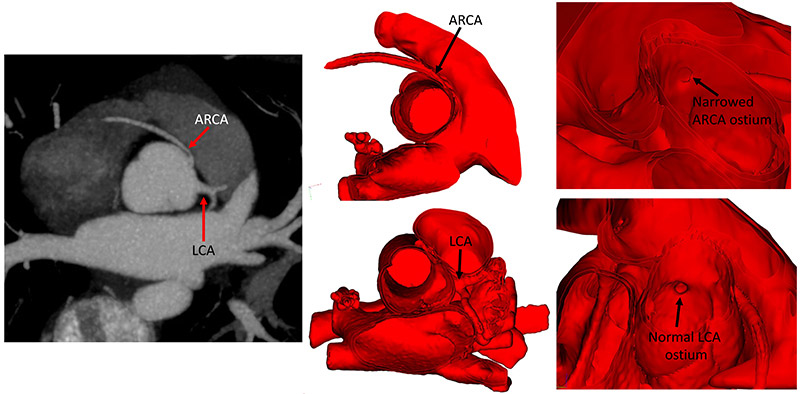

Cardiac CT image (left) demonstrates an anomalous right coronary artery (ARCA) and a normal left coronary artery (LCA). 3D digital modeling of the ARCA and LCA clarify the spatial anatomy as seen from the inside of the heart (middle). Ostial narrowing of the ARCA is clearly seen from the inside of the aorta on the 3D model (right). (Courtesty of Dr. Kanwal Farooqi)

According to the authors, the 3D models were much more accurate in demonstration of a separate AAOCA ostium, 97.4 percent vs. 65 percent on echo and 67 percent by CT. The accuracy of assessment for ostial stenosis was also highest for 3D models, albeit at 56 percent.

“Our 3D digital models, which can also be 3D printed, were able to capture the opening of the coronary artery more clearly, providing an enhanced view of the ostium,” explains Dr. Farooqi. “When this area is narrowed, we believe that the patient is at increased risk for sudden cardiac death. It is challenging to decide if surgery should be performed in patients with anomalous right coronary arteries. The subtle information we gain from 3D digital models augments other clinical data to help us make these critical decisions.”

“There is a lot of controversy about whether to operate in this subset of patients with anomalous aortic origin of the right coronary artery,” says Dr. Bacha. “The imaging work of Dr. Farooqi is helping us to make this decision based on specific criteria. For example, if there is ostial narrowing, it would push us toward operating, and if the ostium does not appear stenotic, then we would not operate.”